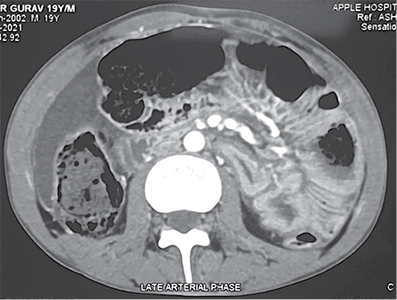

He was resuscitated with 1 500 ml of crystalloids through a left subclavian central line. Contrast-enhanced CT of the abdomen revealed perforation of the urinary bladder and extravasation of free urine into the pelvic cavity. It also revealed pneumointestinalis and grossly dilated bowel loops till mid transverse colon. There was a cut-off point at the level of the mid transverse colon (Figure 1).

Figure 1. Contrast enhanced computed tomography abdomen pelvis showing A – axial view showing dilated ascending colon, proximal transverse colon, intraperitoneal fluid collection B – extravasation of urine inside peritoneal cavity with pelvic collection